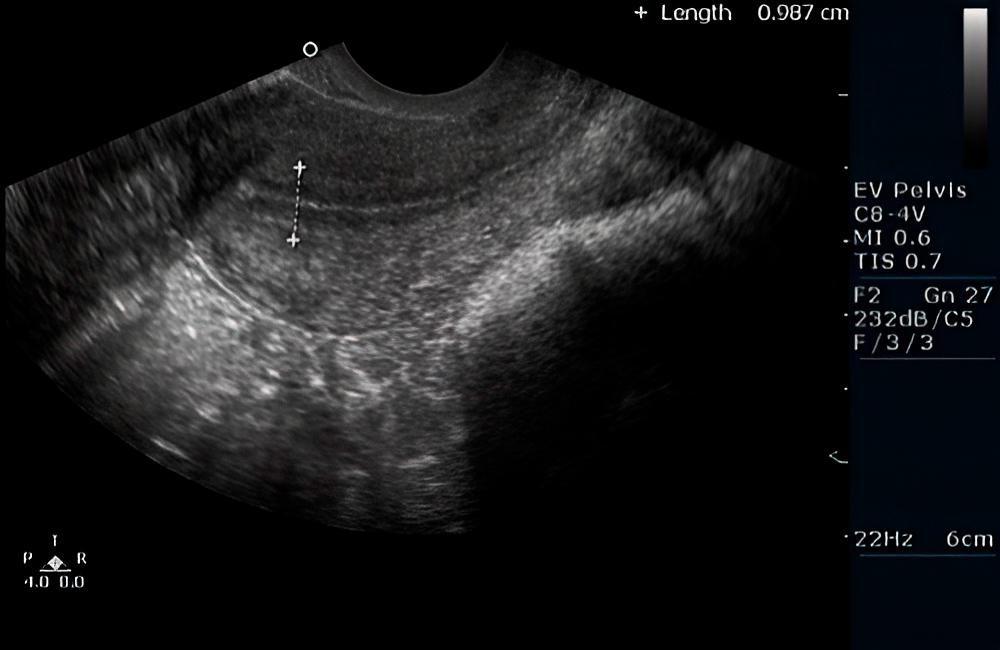

En la tercera imagen, el ovario y el folículo dominante en maduración son visibles, y se asemejan a un óvalo oscuro e irregular. En el cuadrante izquierdo del folículo, parece que puede haber un tubérculo portador de óvulos, el cual constituye la base del futuro huevo.